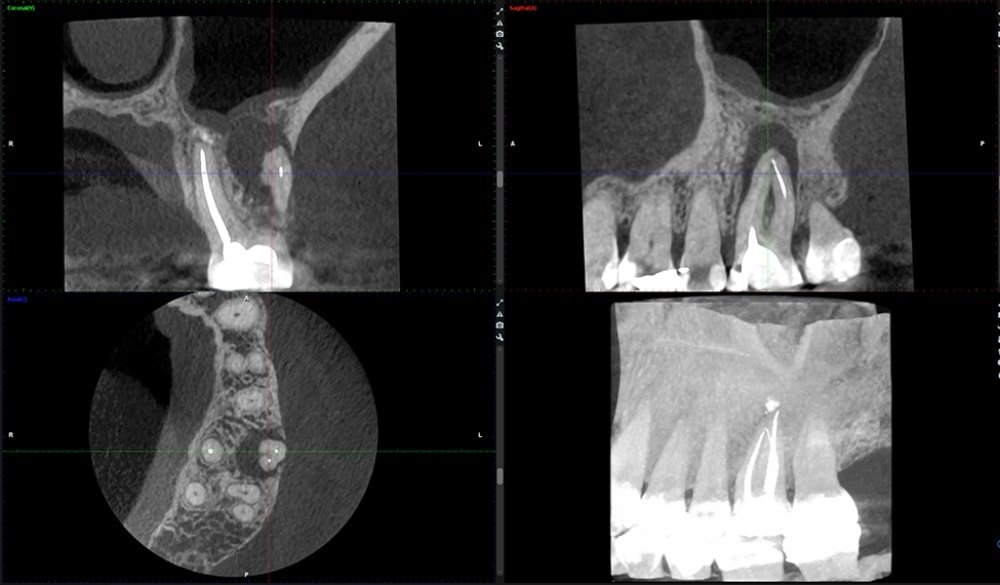

CONEBEAM ou (Scanner)

Le cabinet est équipé d’un appareil de radiographie haute technologie :

un tomographe volumétrique numérique, connu également sous le nom de scanner 3D.

Dans le cas d’un bilan pré-implantaire ou dans le cas de recherche de foyers infectieux, un bilan radiographique 3D est indispensable au docteur Alexandre ORLICK

En une seule prise de cliché 3D, le scanner offre un bilan détaillé.

Il permet de visualiser en 3 dimensions, l’ensemble de votre massif facial particulièrement les maxillaires et les dents.

Il facilite le diagnostic des maladies parodontales, la planification des implants, les interventions chirurgicales de même que les extractions des dents de sagesse. Il permet également la visualisation de kystes.